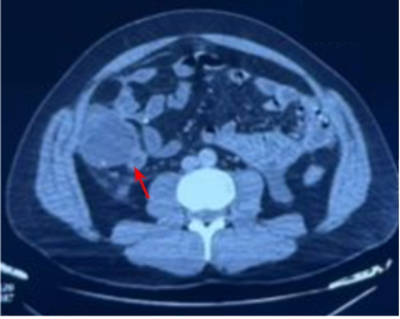

After 48 hours, the patient showed clinical and biological deterioration: ongoing abdominal pain, persistent cloudy effluent, and development of bowel obstruction symptoms (absence of stool and gas). An abdominal X-ray showed diffuse colonic gas without air-fluid levels. An abdominal CT scan revealed acute latero-cecal appendicitis, characterized by cecal fluid distension extending to the ascending colon (measuring 56 mm), with the PD catheter still in place in the pelvis ( Figure 1:).

Figure 1:CT scan image confirming the diagnosis of acute appendicitis (red arrow)